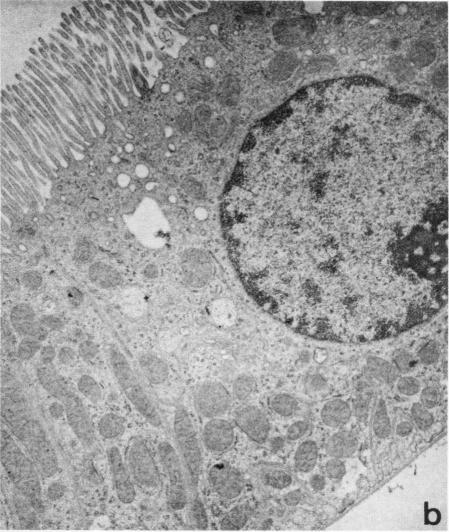

Previous studies in the mammalian proximal tubule have suggested that para-aminohippurate (PAH) secretion is approximately threefold greater in the straight segment, or pars recta, than in the convoluted segment, or pars convoluta. However, the possibility that the site of maximal PAH secretion might be related better to particular tubule segments as identified by cell type had not been explored. In addition, the presence or absence of differences in PAH secretion between morphologically identical regions of superficial (SF) vs. juxtamedullary (JM) proximal tubules has not been examined. These issues were studied using a combination of histologic methods and measurement of [(3)H]PAH secretion in isolated perfused tubules. Measurements of microdissected SF and JM proximal tubules from young and adult rabbits revealed that SF proximal tubules were slightly but significantly longer than JM tubules ([young rabbits: SF, 8.69+/-SE 0.14 mm vs. JM, 7.97+/-SE 0.13 mm; P < 0.01] [adult rabbits: SF, 10.61+/-SE 0.28 mm; JM, 9.17+/-SE 0.19 mm; P < 0.001]). Light and electron microscopy revealed three sequential segments (S(1), S(2), and S(3)) along the length of SF and JM proximal tubules as defined by cell type. PAH secretion was measured in each of these three segments by the isolated perfused tubule technique. Net PAH secretion in fmol/mm per min in SF proximal tubules was: S(1), 281+/-SE 21; S(2), 1,508+/-SE 104; S(3), 318+/-SE 46. Corresponding values in JM proximal tubules were 353+/-SE 31, 1,391+/-SE 72, and 188+/-SE 23. Net PAH secretion did not differ between comparable segments of SF and JM proximal tubules. It is concluded that differences in PAH secretion along the proximal tubule correlate best with cell type rather than the arbitrary division of the proximal tubule into pars convoluta and pars recta according to its external configuration. Evidence of functional heterogeneity between comparable segments of SF and JM proximal tubules was not observed.